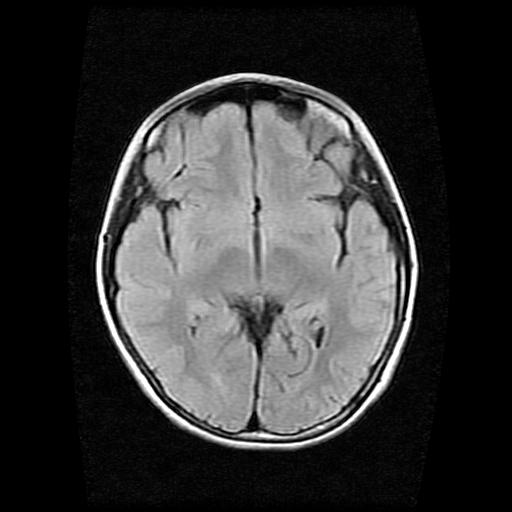

9岁女孩,三岁时诊断为癫痫,一直服丙戊酸钠,现患者一般情况良好,家长复查核磁片,看能否停药..

巨脑回

停药要结合临床,如无发作可以停。